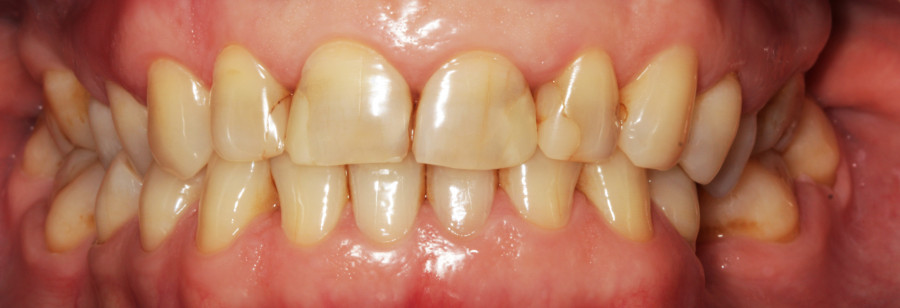

Do kliniki Stomatologia Bez Bólu zgłosiła się pacjentka, lat 61 z problemem nadwrażliwości zębów. Po przeprowadzonym wywiadzie stwierdzono spożywanie sporej ilości sezonowych owoców (truskawki, wiśnie, czereśnie, czarna porzeczka), nawet 3 razy dziennie. Następnie wykonano badanie wewnątrzustne. Stwierdzono obecność płytki nazębnej, ciemnego osadu oraz kamienia nazębnego na części trzonowców:

Wykonano higienizację jamy ustnej poprzez usunięcie kamienia nazębnego skalerem ultradżwiękowym, zdjęciem osadu i płytki nazębnej poprzez piaskowanie air flow plus oraz classic, a następnie wypolerowaniu gumką ze specjalistyczną pastą polerską:

Po wypłukaniu jamy ustnej przez pacjentkę rozcieńczonym eludril classic przystąpiono do fluoryzacji preparatem clinpro varnish. Odizolowano wałeczkami ligniny zęby od śliny aby zapewnić ich suchość, a następnie pędzelkiem nałożono preparat na wszystkie zęby:

Celem fluoryzacji jest zmniejszenie nadwrażliwości zębów oraz wzmocnienie ich przez odbudowę mikroubytków szkliwa.

Lekarz pokazała na modelu sposób szczotkowania i nitkowania. Pacjentce wniesiono niewielkie poprawki w sposobie szczotkowania (ruchy wymiatające). Zalecono stosowanie pasty elgydium anti-plaque i elgydium sensitive naprzemiennie oraz płyn do płukania eludril care zapobiegający powstawaniu płytki nazębnej. Ważne, aby pacjentka zakupiła nową szczoteczkę o miękkim włosiu, aby bakterie znajdujące się na używanej szczoteczce nie przeniosły się na oczyszczone zęby.